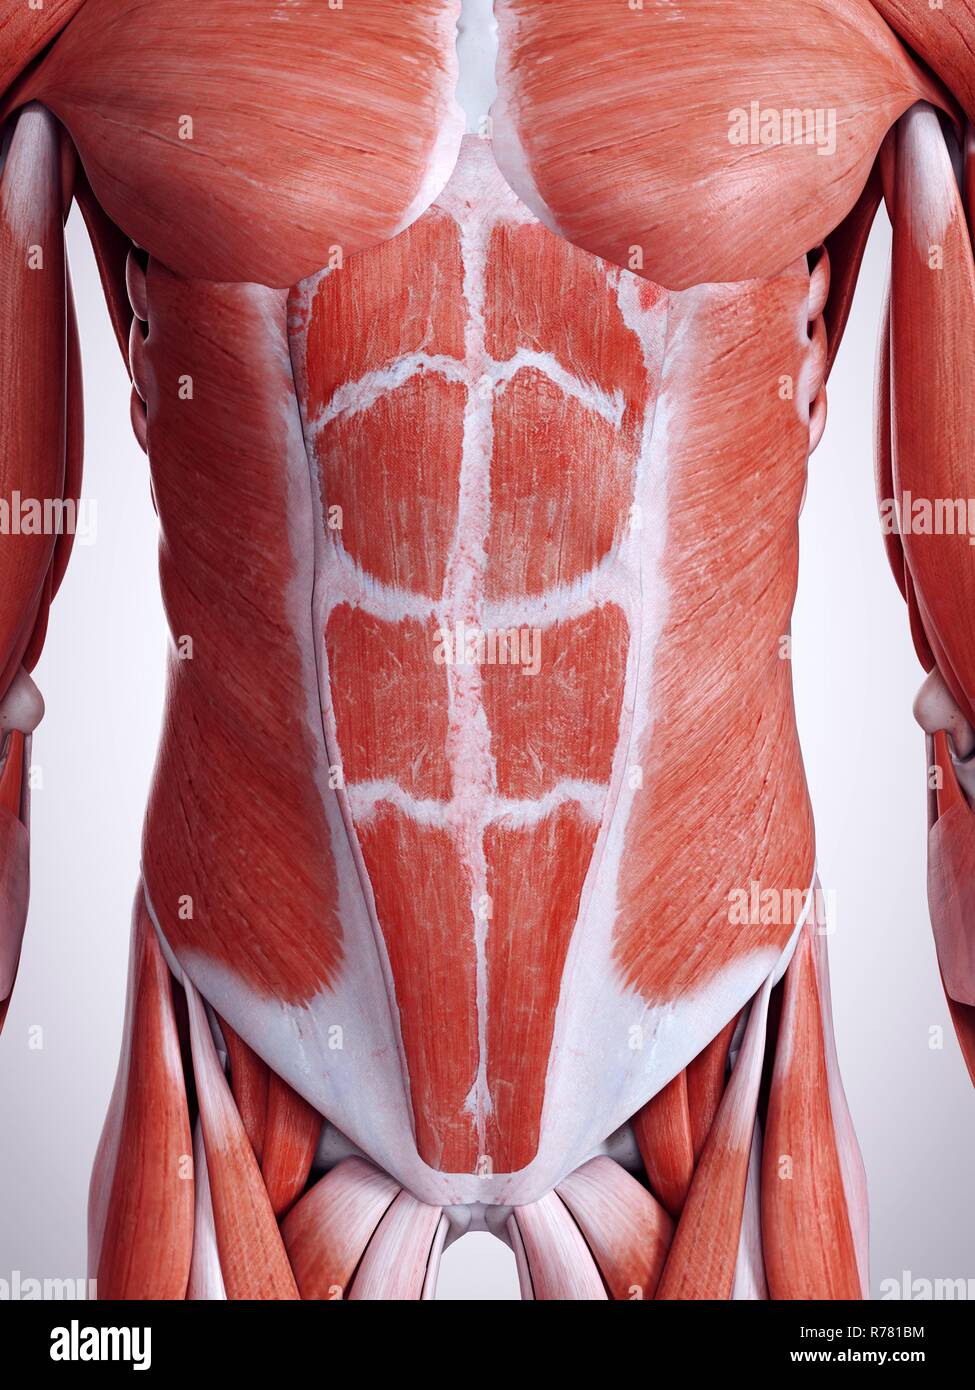

Human Muscles Abdomen Muscles Anatomy Medical Stock Illustration

3d Rendered Illustration Of The Abdominal Muscles Stock Photo - Alamy

www.alamy.comabdominal

www.alamy.comabdominal

Male muscle anatomy of the abdominal wall poster print (26 x 30. Abdomen (human anatomy). 3d rendered illustration of the abdominal muscles stock photo